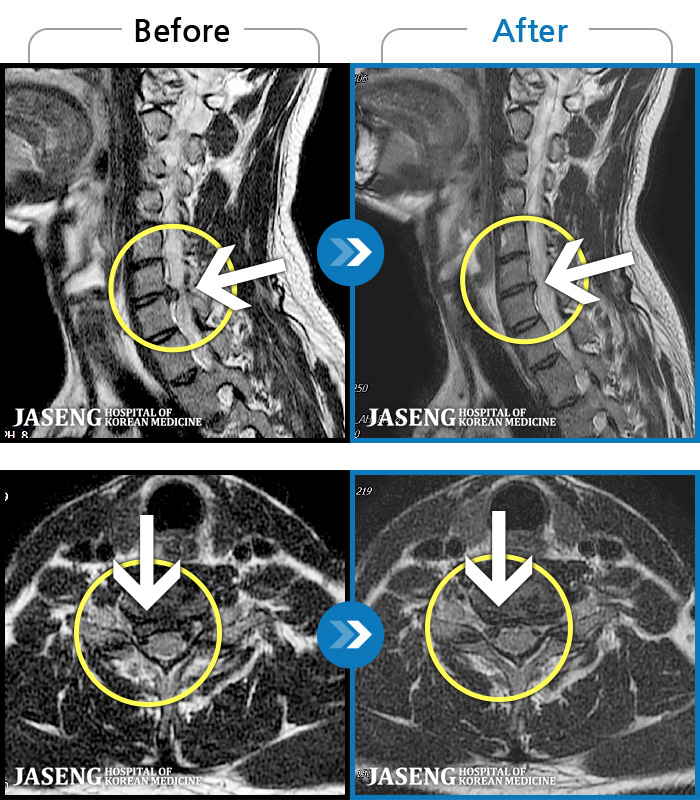

MRI ġ

1,304 MRI ũ ʸ Ȯϼ.